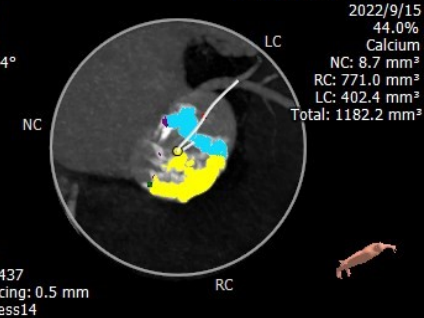

钙化指数:1182.2mm³

主动脉瓣钙化分布

• 主动脉瓣重度钙化,钙化主要分布于瓣叶及瓣叶交界处;钙化从瓣环延伸至流出道9.7mm;